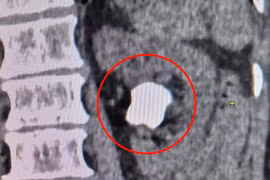

ha-duong-huyet.png

Đo đường huyết để kiểm tra - Ảnh minh họa BVCC